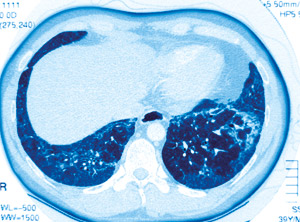

Pasienter med terminal lungesvikt får i økende grad utført bilateral lungetransplantasjon.

Det er uklart hvorfor et økende antall pasienter med idiopatisk lungefibrose og terminal lungesvikt får utført bilateral fremfor unilateral lungetransplantasjon. Randomiserte studier foreligger ikke.

I perioden 1987–2009 fikk 3 327 pasienter med idiopatisk lungefibrose utført lungetransplantasjon i USA, hvorav 36 % var bilateral lungetransplantasjon (1). Median overlevelsestid var lengre etter bilateral transplantasjon enn etter unilateral (5,2 år versus 3,8 år), men det var ingen forskjell etter justeringer for preoperative forskjeller. Forfatterne konkluderer med at bilateral lungetransplantasjon gir flere tidlige komplikasjoner, men bedre overlevelse på lengre sikt. Tilsvarende gir unilateral lungetransplantasjon bedre overlevelse på kort sikt, men risikoen for senkomplikasjoner er økt.